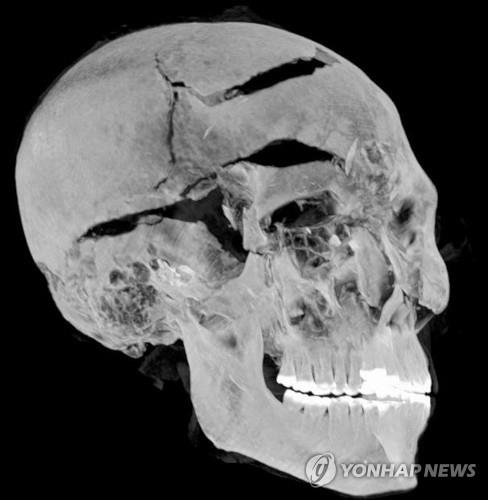

| ▲ 컴퓨터 단층 촬영된 세케넨레 타오 2세 미라의 머리 부분 [이집트 관광유물부 제공=연합뉴스] |

| ▲ 컴퓨터 단층 촬영한 세케넨레 타오 2세 미라의 머리 부분 [epa=연합뉴스] |

이집트 유물부 장관을 지낸 저명 고고학자 자히 하와스와 카이로대 의대 방사선과 사하르 살림 교수는 컴퓨터 단층촬영(CT) 사진으로 미라의 3차원 입체 이미지를 만들었다.

이집트 관광 유물부는 17일(현지시간) "CT 촬영을 통해 기존에 발견된 손상 부위 이외에 다수의 미세한 두개골 손상을 찾아냈다. 이 손상된 부위들은 방부처리 기술자에 의해 교묘하게 가려져 있었다"고 밝혔다.

하와스 전 장관과 살림 교수는 또 도끼와 창, 단검 등 카이로 박물관에 소장된 힉소스 무기들의 생김새와 두개골에 생긴 파손 부위의 모양을 비교해 연관성을 찾아냈다.